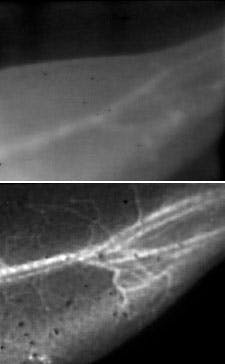

The fluorescence technique, called near infrared-II imaging (NIR-II), involves first injecting water-soluble carbon nanotubes into the living subject's bloodstream. The researchers then shine a laser with NIR light (a wavelength of about 0.8 µm) over the subject; in this case, a mouse. The light causes the specially designed nanotubes to fluoresce at a longer wavelength of 1â1.4 µm, which is then detected to determine the blood vessels' structure.

The fact that the nanotubes fluoresce at substantially longer wavelengths than conventional imaging techniques is critical in achieving the stunningly clear images of the tiny blood vessels: longer wavelength light scatters less, and thus creates sharper images of the vessels. Another benefit of detecting such long wavelength light is that the detector registers less background noise since the body does not does not produce autofluorescence in this wavelength range.

The ability to obtain both blood flow information and blood vessel clarity was not previously possible, and will be particularly useful in studying animal models of arterial disease, such as how blood flow is affected by the arterial blockages and constrictions that cause, among other things, strokes and heart attacks.